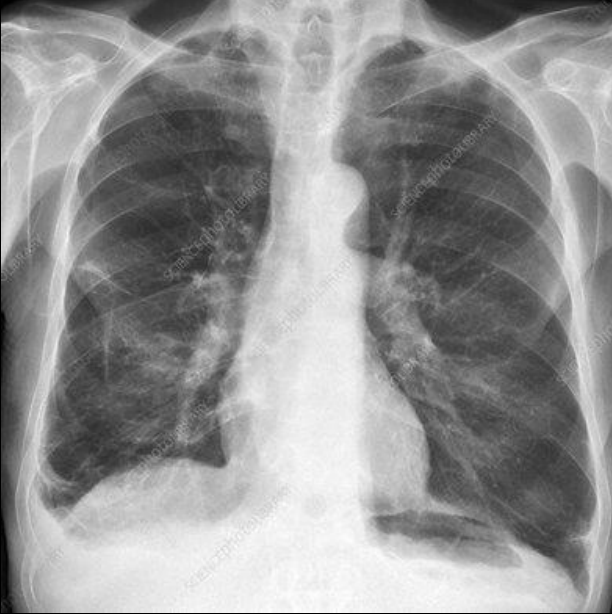

Rx y TC en bronquitis cronica

Patron intersticial

Patrones en tranvia

Engrosámiento peribronquial

Bronquitis crónica